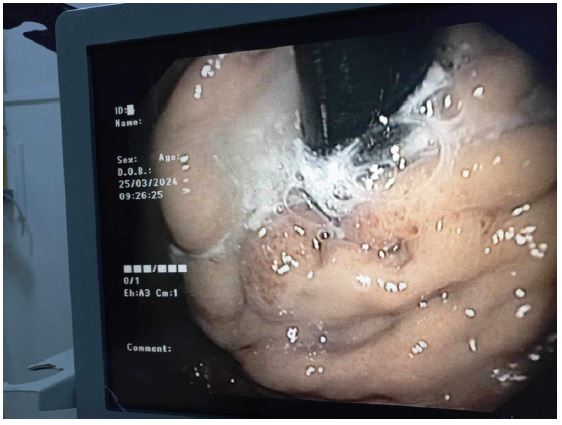

The patient received intravenous Sandostatin and proton pump inhibitors. Upper GI endoscopy revealed mild portal hypertensive gastropathy and a large gastric varix with red signs in the fundus, extending to involve esophageal varices (GOV 2), as per Sarin classification (Figure 1) [3]. Endoscopic sclerotherapy was performed with an injection of 1.5 ml N-Butyl-2-cyanoacrylate (Glubran®) diluted (50/50) with lipiodol into the fundic varix with red signs, under general balanced anesthesia. Airway management and intubation were uneventful. Injection sclerotherapy achieved successful hemostasis, maintaining stable hemodynamic and respiratory status throughout the procedure.

Figure 1: Retroversion view from an upper GI endoscopy showing a large gastric varix with red signs in the fundus.